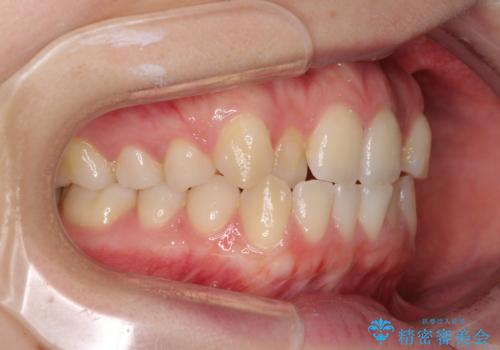

前歯のクロスバイトをインビザライン矯正で改善

- 前歯のデコボコと上下のクロスバイトを気にして来院された患者様です。

インビザラインを用い、IPR(歯と歯の間を削る)と歯列全体を拡大させることで、歯並びを整えていくこととしました。

上の前歯が下の前歯を乗り越える際、奥歯がほとんど咬めない時期があり、乗り越えた後も、インビザライン特有の奥歯の咬みにくさが続きました。

咬み合わせ改善のために治療期間を要しましたが、最終的に奥歯はしっかりと咬めるようになりました。